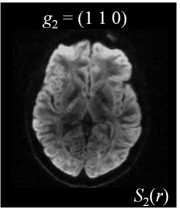

Six axial DW measurements and one non-DW image are shown in Figure 1, along with the corresponding magnetic field gradients . Note the difference in intensity values for different gradient directions.

| (a) | (b) | (c) | (d) |

| (e) | (f) | (g) | (h) |